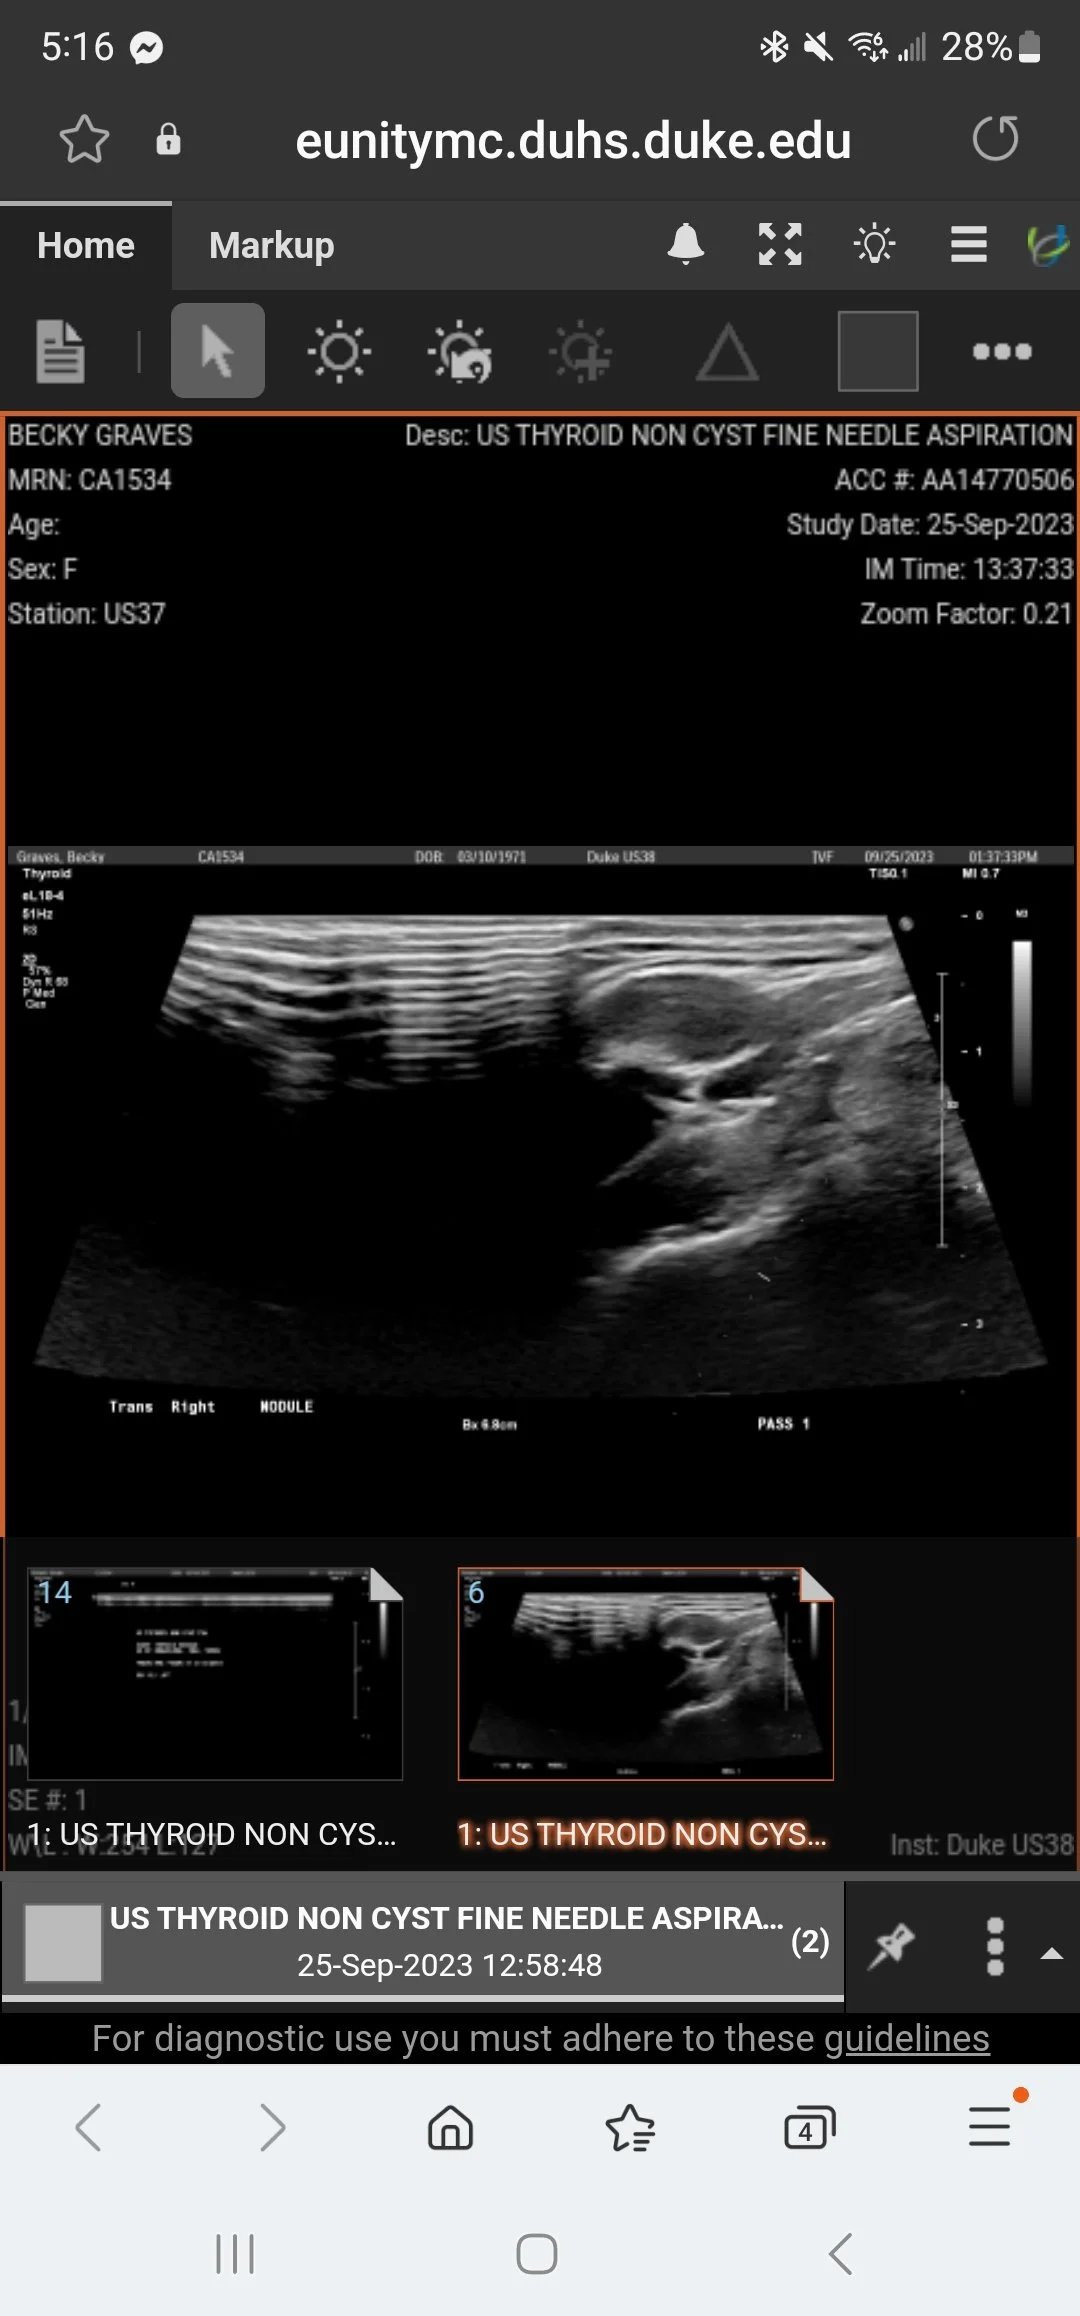

1 p.m. - Thyroid Biopsy

So, no one warned me. A thyroid biopsy is no joke.

I’m not kidding. The biopsy was more painful than anticipated, though in the grand scheme of things it doesn’t even compare with some of the things I’ve already done. Part of the issue was the Lidocaine did not work the way it was supposed to, plus they needed to go in three times - the 3rd time with larger needle. And I felt pain every single time they punctured the thyroid.

After they’d gone in the 2nd time and decided they need to go in a 3rd time, I had to ask for a short break to gather myself because I really thought I might pass out. Thankfully, I did not, and on the 3rd attempt they got an adequate sample.

• Thyroid Biopsy - indeterminate. Being sent for further testing.